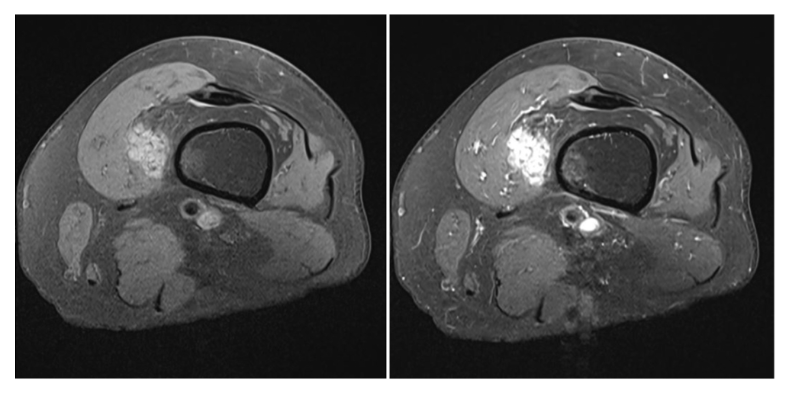

Sequences + pathology?

• T1, STIR, T1FS C+

• Sarcoma within the muscle of the right thigh

• T1 – lacking symmetry between the left and right thigh

• STIR – fluid sensitive scan that has picked up fluid involvement hence,

suggestive of a pathological process.

• T1FS C+ - vascular involvement has there is high signal from contrast

situated inside the sarcoma.